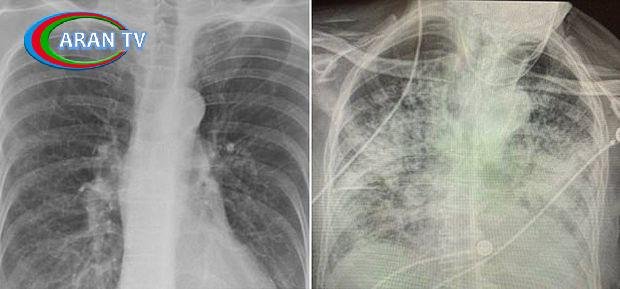

Alimin paylaşdığı rentgen nəticələri diqqət çəkib. Sol tərəfdəki şəkil siqaret çəkən, sağ tərəfdə isə koronavirusdan sağalan insanın ağciyərini göstərir.

Rentgendə qara rənglər nə qədər çox olarsa, deməli həmin insanın ağciyəri və sağlamlığı bir o qədər yaxşıdır.

Əldə edilən nəticədən o qənaətə gəlmək olar ki, koronavirus keçirən insanın ağciyəri siqaret çəkən şəxslərinkindən daha çox zədələnmiş olur.